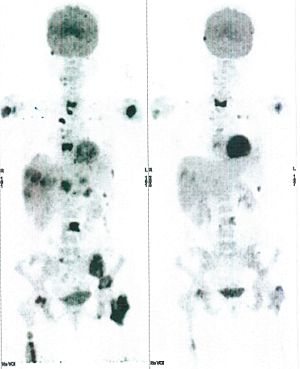

CASE NO: 1 - A FEW MONTHS LATER

A few months after successful treatment for hepatocellular carcinoma, and partially successful for stomach cancer, the PET/CT scan showed the stomach cancer becoming very active, with several metastases to the parts of the liver not previously involved by hepatocellular carcinoma. After a few treatment, all the active stomach cancer lesions in the stomach and in the liver went into remission.